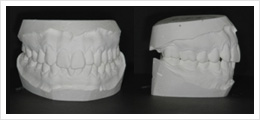

교합기란 위아래 치아가 맞물리는 상태와 씹는 기능을 입 밖에서 그대로 재현할 수 있는 장치입니다.

치아가 맞물리는 것은 입안의 검사만으로도 간단하게 알 수 있지만 턱관절이 제 위치에 있는 상태에서 잘 맞물리고 기능하고 있는 상태인지는 정확하게 알기 어렵습니다.

교합기는 턱관절의 위치를 제 위치로 유도하여 정확한 턱관절의 위치에서 씹는 상태가 어떤지, 기능을 할 때에는 아래턱이 어떻게 움직이는지를 평가할 수 있는 도구입니다.

교합기는 여러 가지 종류가 있지만 그 원리는 거의 동일합니다. 교합기는 교합을 치료하는 치과영역에서 정확한 진단과 치료를 위해 광범위하게 사용되고 있습니다.

교정치료 시 치아의 맞물림 상태를 정확하게 관찰하고 진단하기 위해서 교정용 모형을 제작합니다. 하지만 꼭 물고 있는 교합 상태로 제작한 일반적인 교정용 모형은 꼭 문 상태에서 위아래 치아들이 어떻게 맞물리고 있는지는 알 수 있지만 그 상태에서 아래턱이 턱관절에서 제 위치에 있는지, 씹는 기능을 할 때 아래턱이 어떻게 움직이는지는 알 수 없습니다.

처음부터 정밀한 교합기를 사용하여 교정진단을 하게 되면 제 위치된 턱관절 상태에서 교합 상태를 진단할 수 있어 얼굴 전체의 기능적인 부분까지 고려한 진단결과가 나오게 되며, 교정치료를 보다 올바른 방향으로 진행할 수 있습니다.